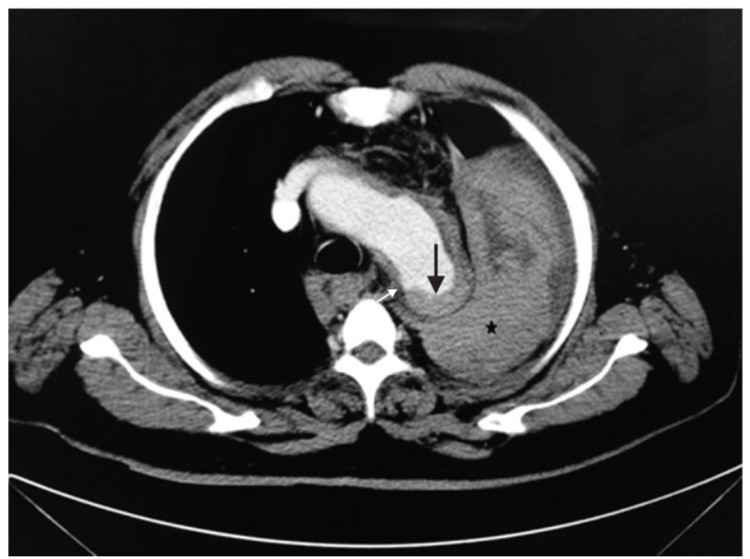

![]() |

| Kết quả chụp CT cho thấy bệnh nhân bị vỡ phình động mạch chủ. Ảnh BSCC |